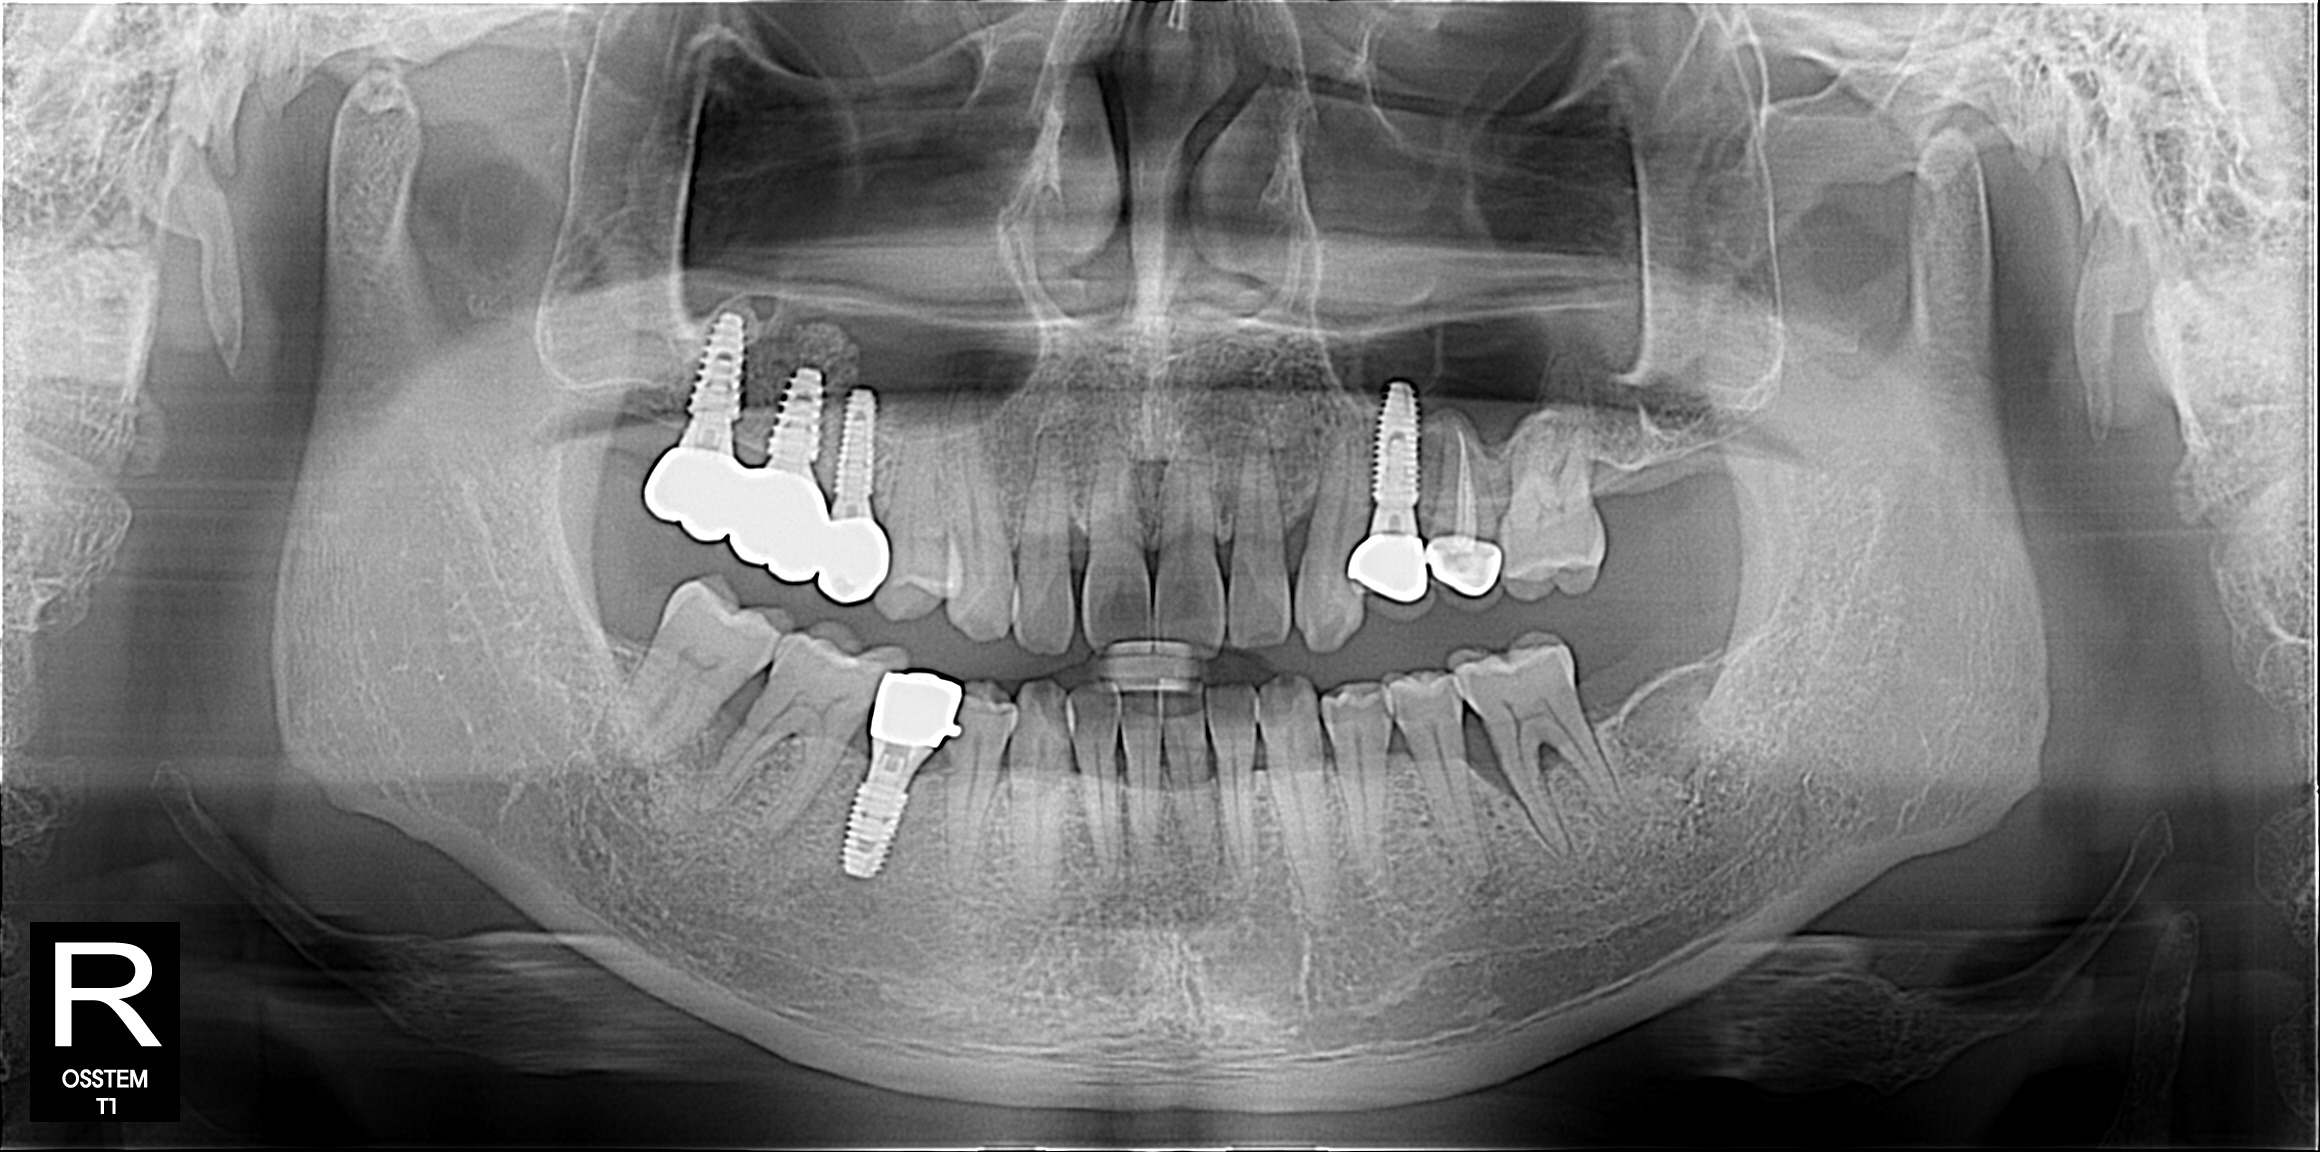

결과로 증명하는

치료케이스

상담부터 사후관리까지

환자 한 분, 한 분의 상태에맞춰 꼼꼼하게 진행합니다.

임플란트

BEFORE & AFTER